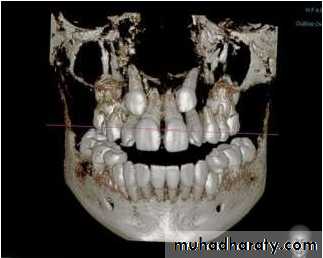

A study was done by Ali Alqerban et al AJODO March

2015, to compare 3D CBCT images of unilaterally

impacted canines with the normal contralateral sides,

and to detect possible radiographic factors involved in

maxillary canine impaction.

Prediction of the probability of canine impaction based

on CBCT was excellent. The canine angulation to the

lateral incisor on the coronal view, the canine cusp tip to

the occlusal plane on the sagittal view, and the canine

crown position were the strongest predictors based on

the CBCT radiographs and may help orthodontists to

identify the probability of impaction for optimally timing

the intervention.

Cone-beam computed tomographyand the orthosurgical management of impacted

teethCBCT imaging can be used to interpret buccolingual

information in detail, to distinguish and define the extent and

depth of root resorption, and to delineate long-axis orientation

of unerupted teeth, including root apex location. It is able to

synthesize traditional panoramic and cephalometric

radiographs. permits oral surgeons to visualize the position

and surgical anatomy of the tooth as it will be seen in the

operating theater and allows orthodontists to plan directional

traction.